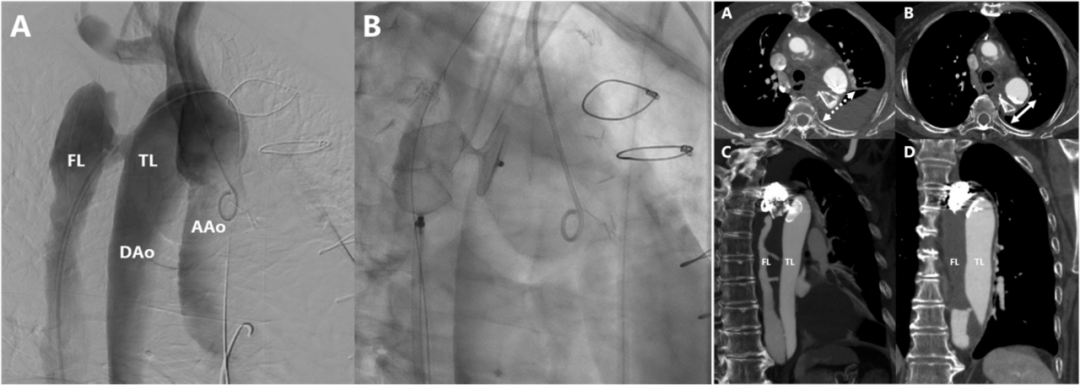

临床医师对Ⅱ型内漏的关注逐渐提高。Ⅱ型内漏的危险因素包括粗大通畅IMA(直径≥2.5 mm)、≥2条腰动脉、瘤腔长度和直径、髂总动脉长度等。目前,对于髂内动脉地处理,比较统一,无非是直接覆盖、栓塞和重建。现有的数据表明,直接覆盖并不能替代栓塞。另外,受解剖限制,IBD/IBE仅适用于约40%的CIA动脉。不仅如此,应用IBD/IBE会增加患者的经济负担,同样不适用于所有患者。受限于疾病本身、器具、技术以及费用等,栓塞ⅡA往往是预防Ⅱ型内漏的最佳选择。

多项研究表明,当通过血管内入路治疗解剖上具有挑战性的主髂动脉瘤疾病时,髂内动脉的栓塞往往是必要且安全的。栓塞髂内动脉不仅是一种安全有效的治疗方法,还增加了腔内修复主髂动脉瘤的适用性。2014年,一项回顾性研究评估2002~2011年间88例在EVAR术前接受了ⅡA栓塞的患者。ⅡA栓塞技术成功率为95.7%,术后38%出现了臀性跛行,10%勃起功能障碍,但无严重臀部缺血并发症。对比单侧和双侧栓塞、同时和分期栓塞,并无统计学差异。在大多数病例中,ⅡA栓塞术是安全有效的,可以防止显著的Ⅱ型内漏。2016年,一项评估EVAR术前栓塞ⅡA盆腔缺血发生率和相关因素的研究,共纳入25例患者,8例(32%)出现新发缺血,包括勃起功能障碍(4%)和臀部跛行(28%),仅4例(16%)持续6个月。进一步分析显示双侧ⅡA栓塞和较短的EVAR时间间隔与风险增加相关(P=0.006和P=0.044)。由此表明,ⅡA栓塞是一种有益的手术,为了最小化臀部跛行的风险,建议不要双侧ⅡA栓塞,适当延长与随后EVAR的时间间隔。2020年,一项纳入了139例主髂动脉瘤患者的回顾性研究,结果表明在EVAR行ⅡA栓塞是安全有效的,大多数患者为未发生(60.0%)或轻度(36.7%)臀部跛行。同年,一项对比ⅡA保留和栓塞疗效的回顾性研究,结果表明ⅡA栓塞技术成功率为100%,ⅡA栓塞常见并发症为臀肌跛行,仅1例ED,无其他严重并发症。4、AVP栓塞ⅡA是一种安全便捷且高效的方法,优于弹簧圈AVP作为栓塞装置,可以促进血液凝固,并对血流形成一道物理屏障,激活机体的免疫系统反应,从而启动机体的自身凝血过程。相较于弹簧圈,AVP是一种可以在高流量血管进行锚定的栓塞材料,更加均匀且致密。

2016年,一项多中心研究分析了2007~2013年间169例接受AVP治疗的临床疗效;研究结果,技术成功率为97.6%,手术平均时长14 min,平均需要1.43个AVP实现栓塞。随访期间未观察到ⅡA再通,证明了AVP的安全性。另外,一项弹簧圈和AVP的对比研究提示,AVP的手术和放射暴露时间更短(59 min vs. 97 min),使用数量更少(1.14 vs. 7.54),治疗成本更低。

另一项对比AVP和弹簧圈栓塞术后并发症的研究,结果显示总的并发症风险较低,常见的是臀部跛行(9.4%)、腹股沟血肿(1.1%)、内漏(5.3%)和勃起功能障碍(1.0%)。而无论是单侧,还是双侧ⅡA栓塞,AVP组臀肌跛行和勃起功能障碍的发生率都低于弹簧圈组。这可能是由于AVP定位准确,不会发生移位,集中于髂内主干,而弹簧圈可能会发生移位,导致栓塞髂内动脉壁支或脏支。此外,AVP成像伪影少,更容易识别可能发生的内漏,不影响EVAR术后影像监测的判断。

5、AVP栓塞ⅡA技术要点

一项纳入2,671例患者荟萃分析评估了ⅡA栓塞治疗对于患者后续的影响;结果表明,近端栓塞可以降低臀部跛行发生率,且AVP组比弹簧圈组并发症少,手术更便捷,造影更少。在两种栓塞技术都可行的情况下,优先考虑AVP,且栓塞尽可能位于ⅡA近端。